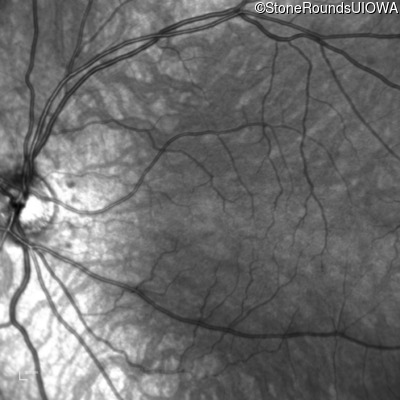

Infrared Fundus Photograph - Right - 20/125

Exemplar